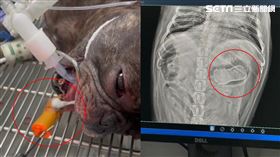

獨/法鬥吞「雞頭卡7天」噴1萬5夾出狂閃

飼主通通都有全體注意!母湯再買mini尖叫雞給你家愛...

2024/08/02 12:09